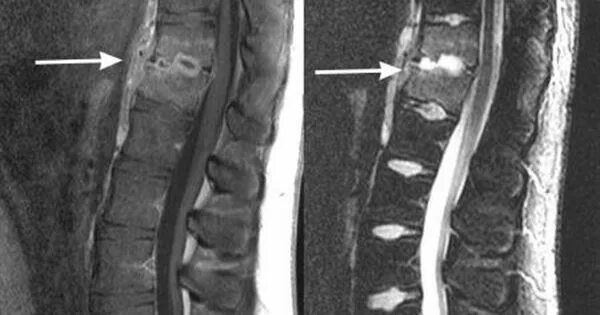

Перелом позвонка инвалидность